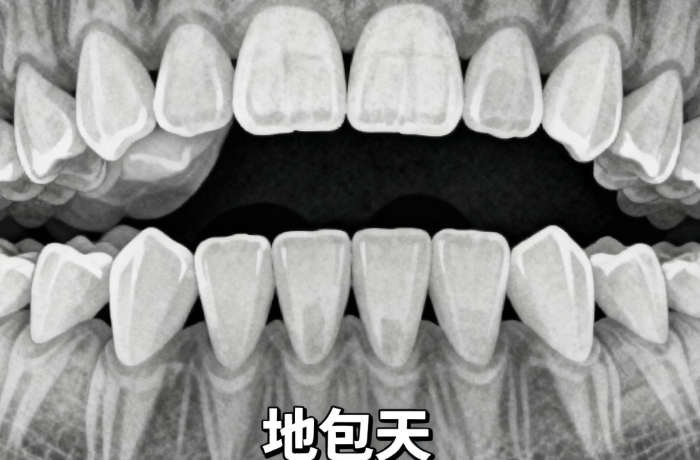

MRC 矫正器对下颌后缩是有用的,尤其针对儿童 / 青少年时期的功能性下颌后缩,是临床常用的早期干预矫正方式;但对成人骨性下颌后缩,仅能做轻微改善,无法达到理想的骨骼调整疗效,核心作用集中在生长发育期的干预矫正。

1. 适用人群:较佳适用年龄为3 - 12岁儿童,适用于替牙期儿童的上颌前突、下颌后缩问题,对均角型下颌后缩疗效较好。

3. 局限性:它对较重骨性反颌疗效有限,高角型下颌后缩患者使用可能导致下颌平面顺时针旋转,加重后缩。并且需要长期佩戴,通常是夜间6点至次日早上7点,还需配合定期复诊。m.59#&w.net